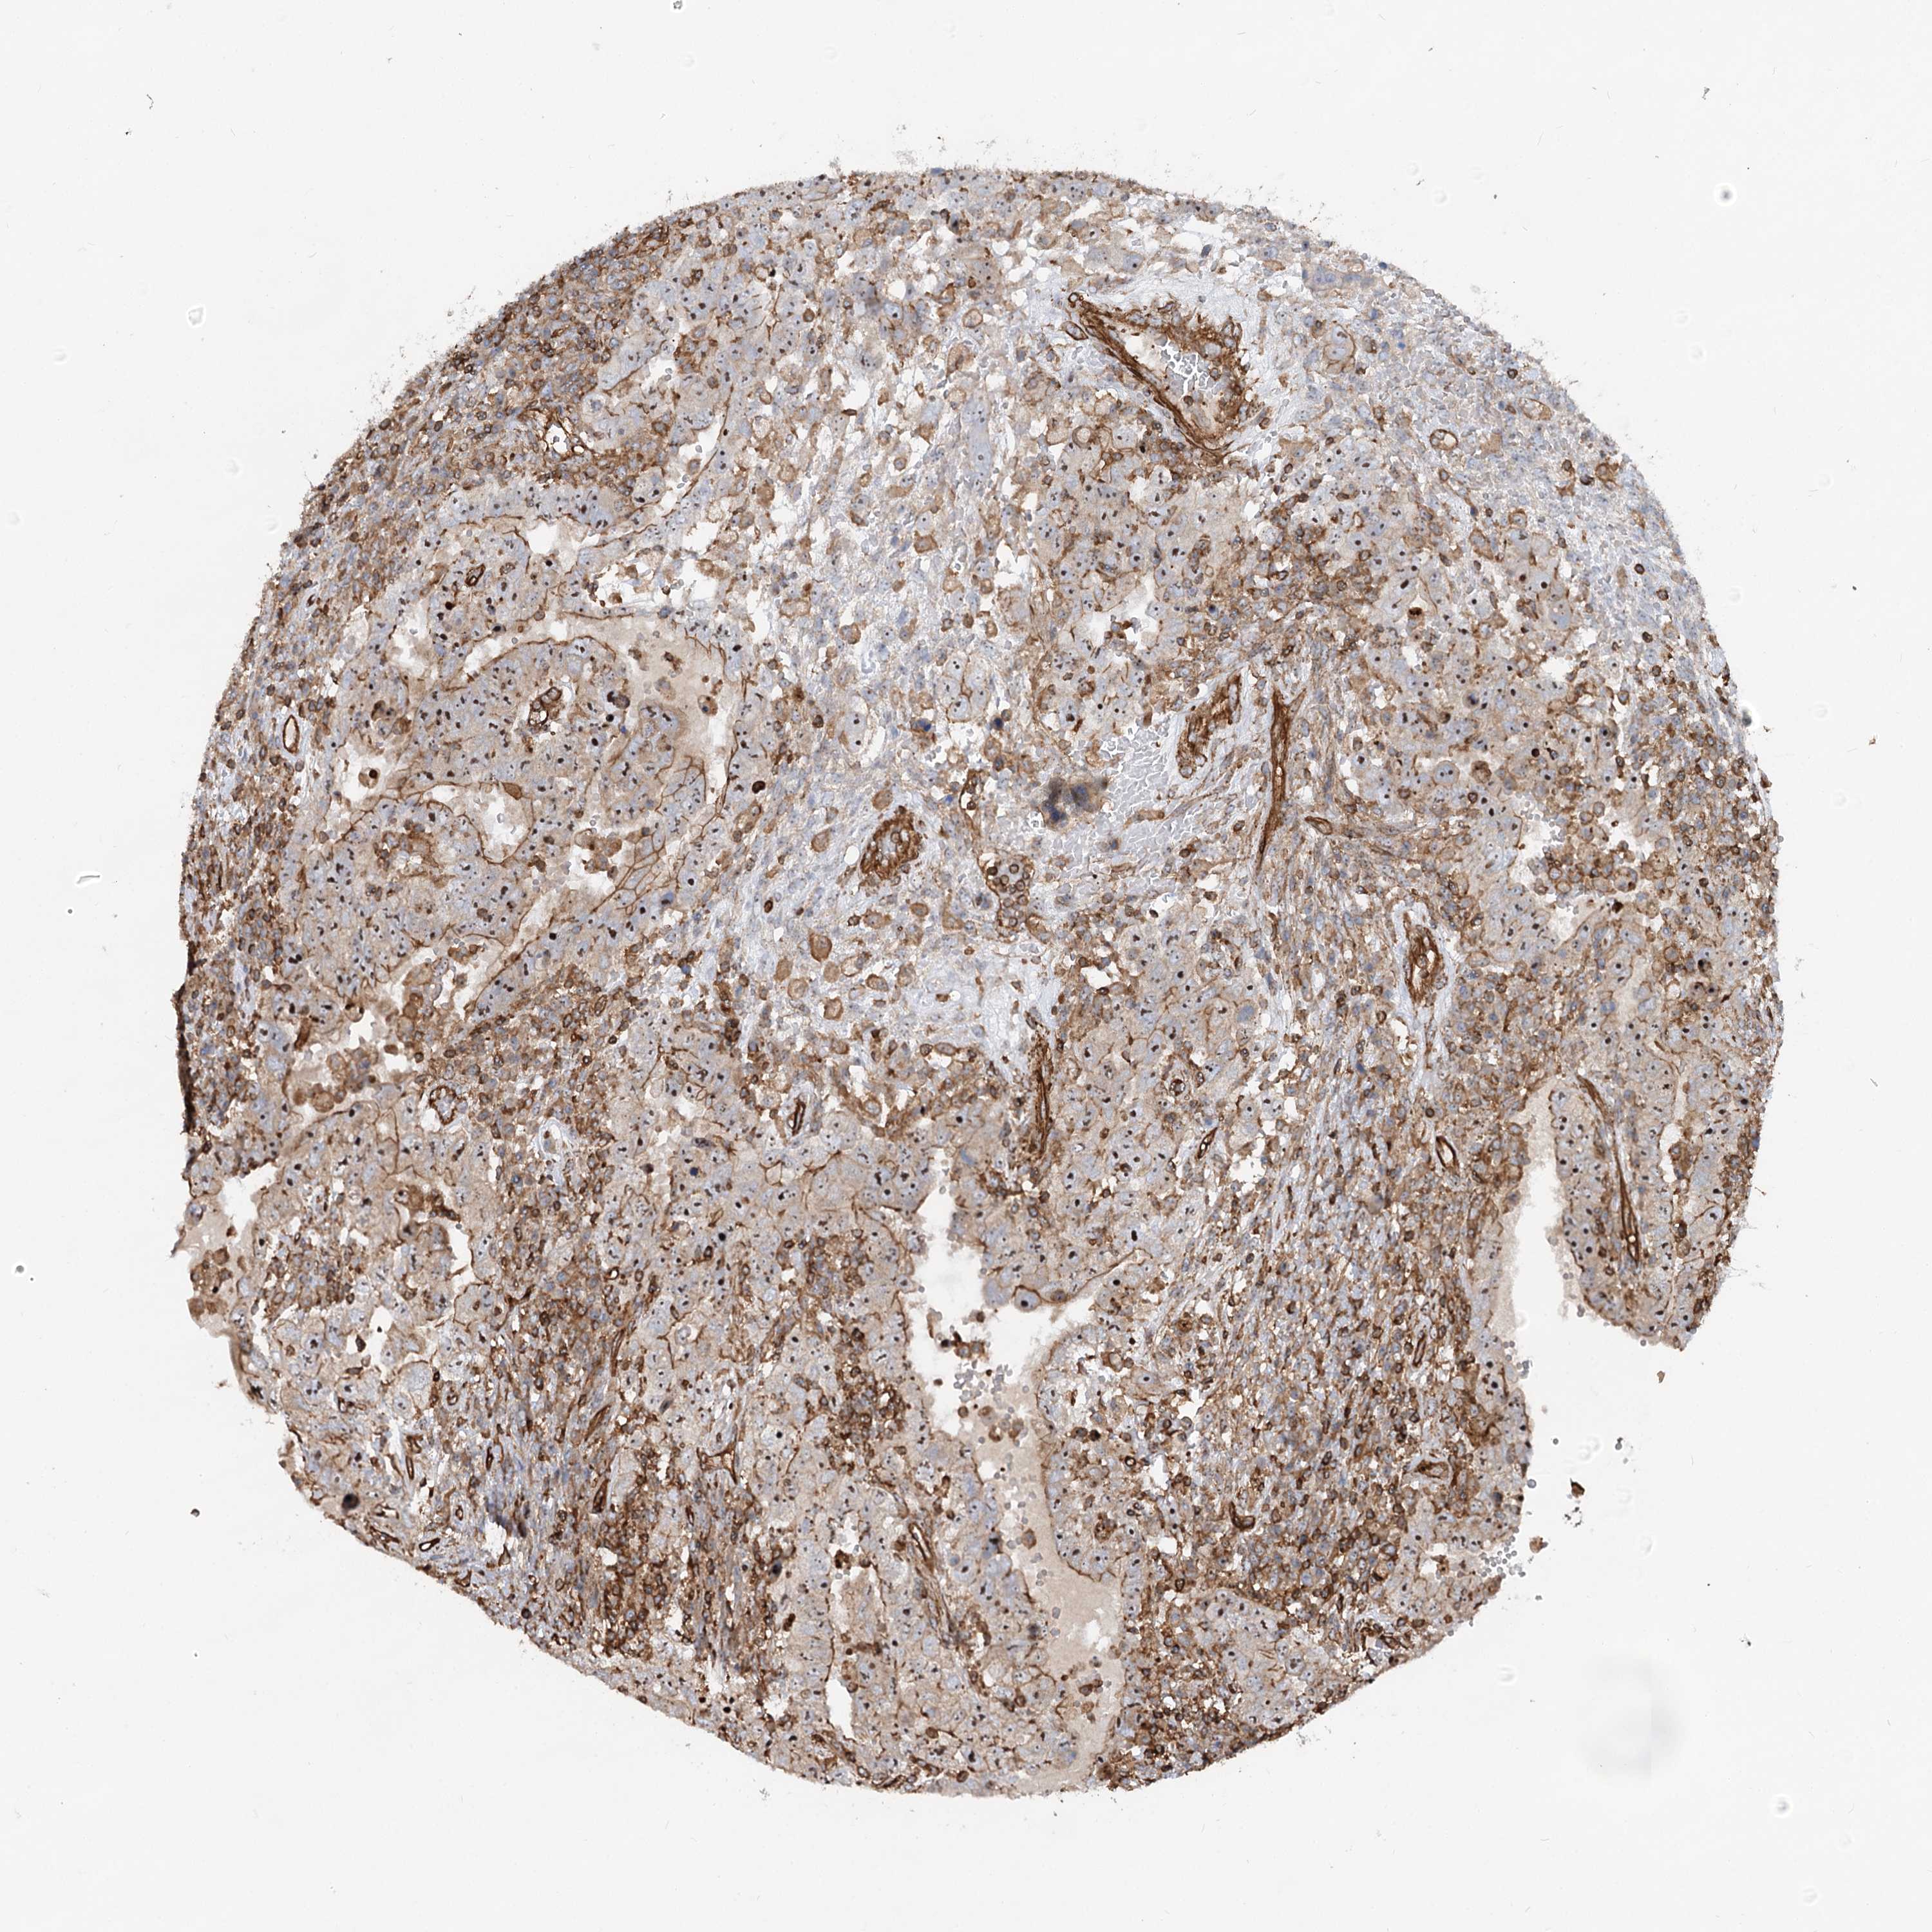

TESTIS CANCER - Protein expressioni

A mouse-over function shows sample information and annotation data. Click on an image to view it in a full screen mode. Samples can be filtered based on level of antibody staining by selecting one or several of the following categories: high, medium, low and not detected. The assay and annotation is described here.

Note that samples used for immunohistochemistry by the Human Protein Atlas do not correspond to samples in the TCGA dataset.

Antibody stainingi

Antibody staining in the annotated cell types in the current human tissue is reported as not detected, low, medium, or high, based on conventional immunohistochemistry profiling in selected tissues. This score is based on the combination of the staining intensity and fraction of stained cells.

Each image is clickable and will lead to virtual microscopy that enables deeper exploration of all samples and also displays staining intensity scores, fraction scores and subcellular localization as well as patient and tissue information for each sample.

Antibody HPA037797

Seminoma, NOS

Carcinoma, Embryonal, NOS